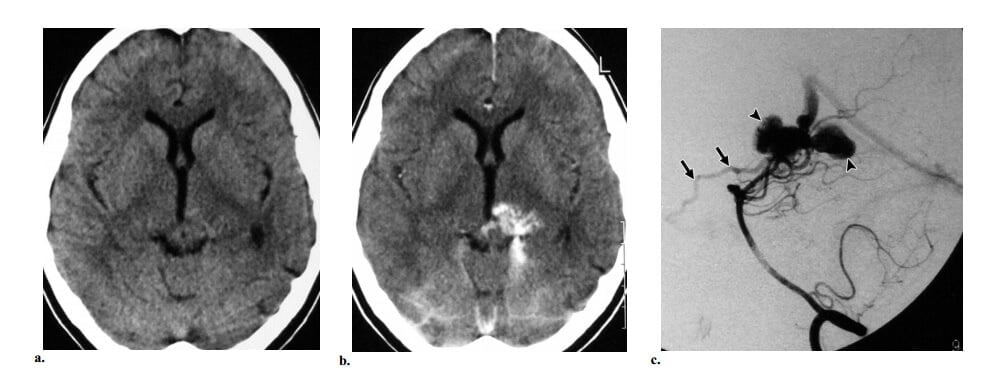

Hình 2: AVM não kiểu nông kinh điển ở bệnh nhân nam 18 tuổi có máu tụ vùng đính trái. (a) Axial cản quang cho thấy một đám rối cấu trúc dạng ống bắt quang mạnh nhúng trong thùy đính trái, một dấu hiệu hợp với nidus. Ghi nhận tăng đậm độ biểu hiện xuất huyết trong não thất. (b) Hình ảnh hướng cường độ tối đa (MIP) (nhì từ đáy) từ dữ liệu chụp mạch CT cho thấy lớn động mạch não giữa trái (so với bên phải), cấp máu cho nidus. (c) Chụp động mạch cảnh trong trái thế nghiêng thấy một nidus kiểu hình cầu ở vị trí vỏ não, được cấp máu chủ yếu bởi nhánh góc và nhánh đính sau của động mạch não giữa trái, với dẫn lưu sớm vào tĩnh mạch vỏ đính trái, các dấu hiệu khẳng định chẩn đoán AVM não.

Hình 3: AVM não kiểu sâu kinh điển ở bệnh nhân nữ 19 tuổi đau đầu đột ngột sau đó mất tri giác. Khám thực thể thấy liệt dây thần kinh VI hai bên. (a, b) Axial CT không cản quang (a) và cản quang (b) các cấu trúc mạch máu bắt quang mạnh ở đồi thị trái. Mặt dù không có bằng chứng xuất huyết trên CT, lâm sàng có nghi ngờ hiều đến vỡ. (c) Chụp động mạch cột sống trái thế nghiêng giúp khẳng định sự hiện diện của AVM đồi thị, được cấp máu bởi động mạch xuyên đồi thị và các nhánh động mạch mạch mạc sau trái và dẫn lưu chủ yếu vào tĩnh mạch Galen và dẫn lưu ít vào tĩnh mạch nền của Rosenthal bên trái (mũi tên). Ghi nhận các túi tĩnh mạch nhỏ (đầu mũi tên), sự hiệndiện của các túi này gợi ý nguy cơ xuất huyết cao.